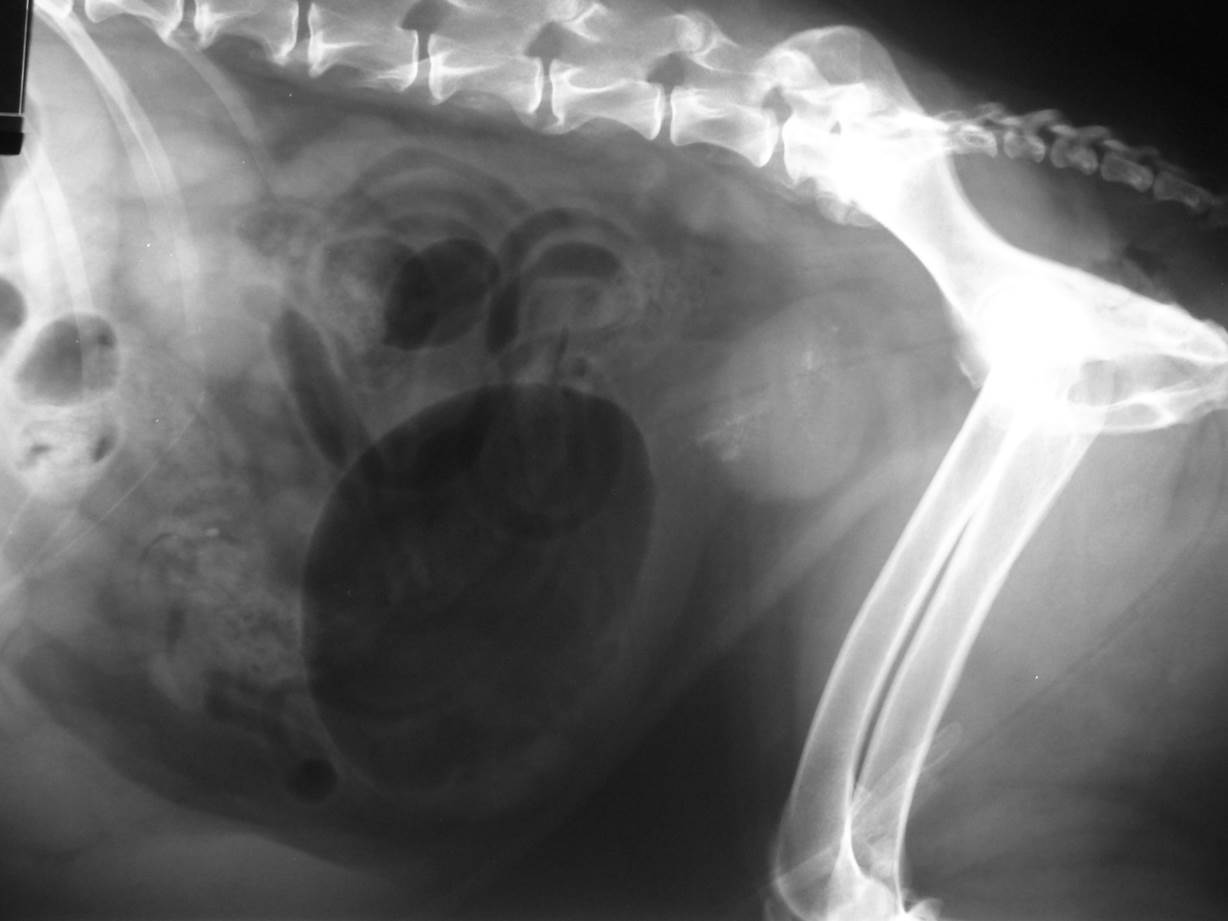

Case Nutty

Discuss this case?

–loss of the normal tear drop shape of the bladder

–urethra relatively short/kinked

–urinalysis including culture

–treatment trial with phenylpropanolamine +/- estriol